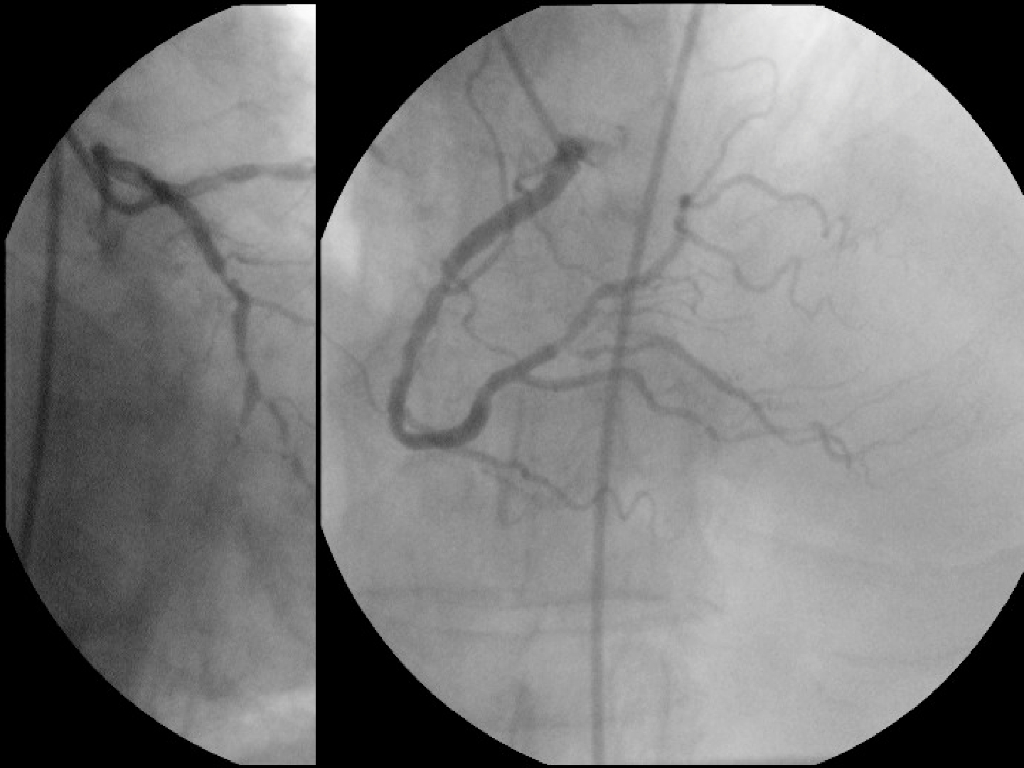

《放射诊断学》演示文稿-高心、肺心、冠心病--实习.pdf